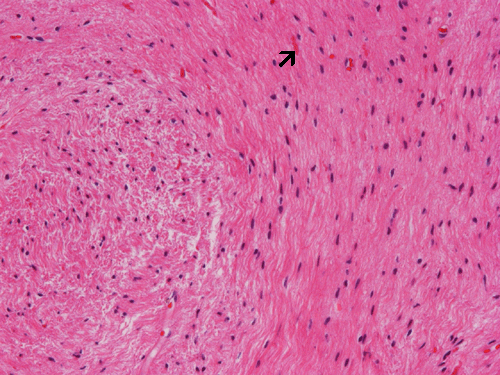

Reactive gliosis: This image was obtained from an area with reactive gliosis around the cystic component of a craniopharyngioma. Note that there is no atypia or pleomorphism in the reactive astrocytes and there are also Rosenthal fibers (arrow). Without a clinical suspicion or knowledge of clilnical information, this histopathologic picture may suggest pilocytic astrocytoma on frozen sections or small biopsies where the craniopharyngioma component is not present.